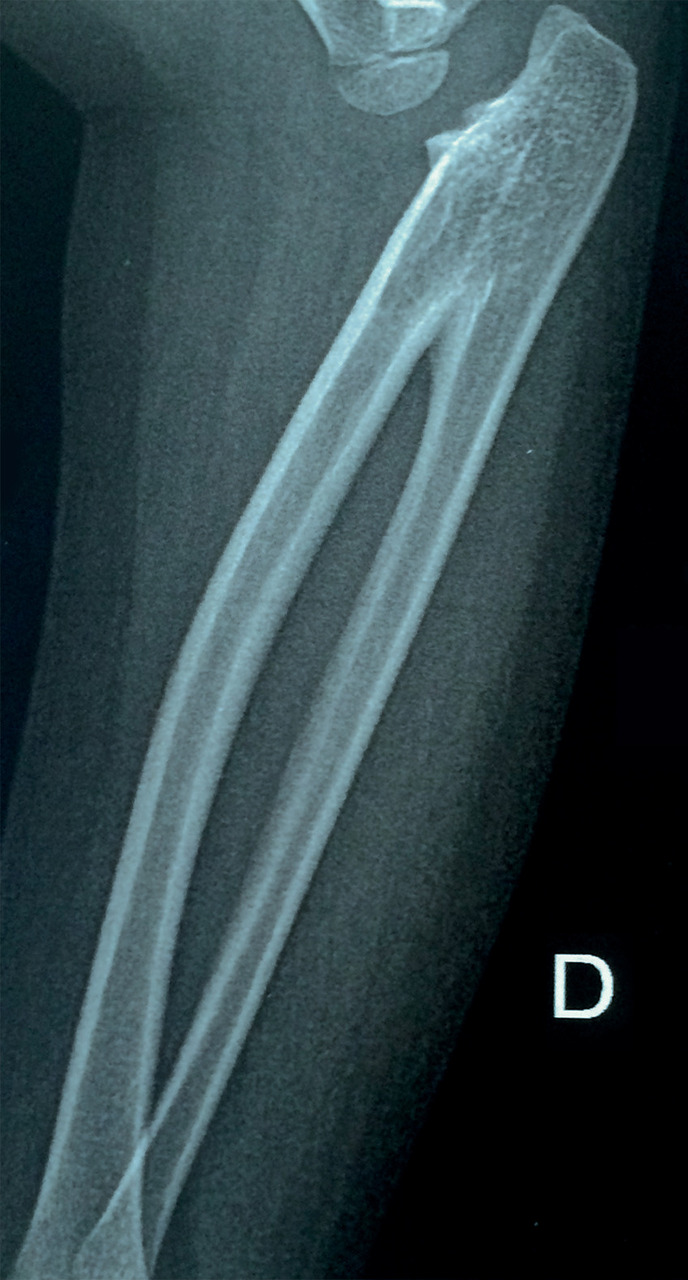

À la radiographie de l’avant-bras et du coude : fusion des parties proximales de radius et de l’ulna (fig. 1 et 2).

La synostose radio-ulnaire congénitale, avec fusion plus ou moins complète des épiphyses proximales du radius et de l’ulna, est une affection rare : environ 350 cas recensés dans la littérature. Elle est bilatérale dans 60 % des cas, et prédomine chez les hommes (3 pour 2 femmes).

Parfois associée à d’autres malformations (aplasie du pouce), voire aux syndromes de Carpenter, d’Apert ou de Klinefelter, elle correspond à un défaut de séparation embryonnaire des os vers la cinquième semaine de développement. Le pont cartilagineux s’ossifie et fixe l’avant-bras en pronation. Les muscles supinateurs et pronateurs sont anormaux ou absents, la membrane interosseuse épaissie. La tête radiale peut être hypoplasique, luxée ou absente, et l’épiphyse ulnaire distale déformée.